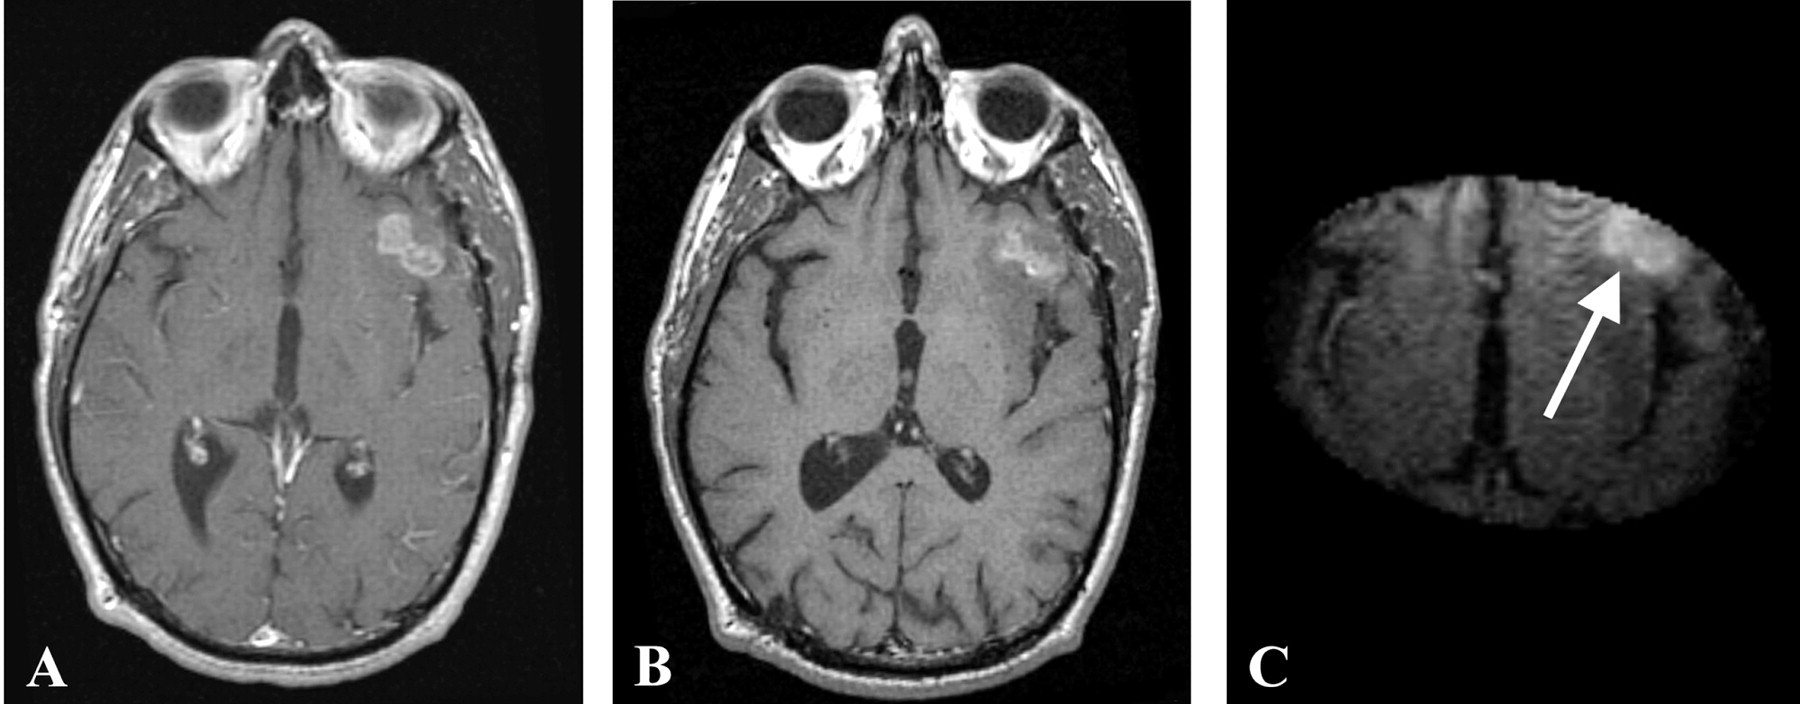

Both patients underwent IMRI-guided resection of their tumors. Preoperative MR imaging demonstrated the targeted lesion. Intraoperative MR without gadolinium, following the prior administration of ferumoxtran-10, easily provided images that demonstrated the lesions seen on preoperative MR images obtained in both patient 1 (Fig 1) and patient 2 (Fig 2). In one operation, post-resection imaging revealed a persistently enhancing area that was then resected (Fig 3). Even in the low-field-strength IMRI system, ferumoxtran-10 provided adequate imaging of the lesions in both of these patients. Postoperative MR images obtained in both patients had no significant enhancement with gadolinium, which suggests resection of the enhancing tumor bulk (Figs 4 and 5). Both postoperative MRIs show high T1 signal intensity in the wall of the resection cavity. The walls of the cavities, however, do not appear to enhance significantly with gadolinium. Figure 5 also shows the resection cavity itself filled with T1 hyperintense material. The cause of this residual T1 hyperintensity, either from blood or ferumoxtran, is unclear. Iron staining of one patient’s lesion demonstrated iron accumulation within peritumoral reactive cells (Fig 6).

Preoperative gadolinium-enhanced (A), ferumoxtran-10-enhanced (B), and intraoperative ferumoxtran-10-enhanced T1-weighted MR images (C) from patient 2. Panels B and C were obtained approximately 24 hours after ferumoxtran-10 administration.